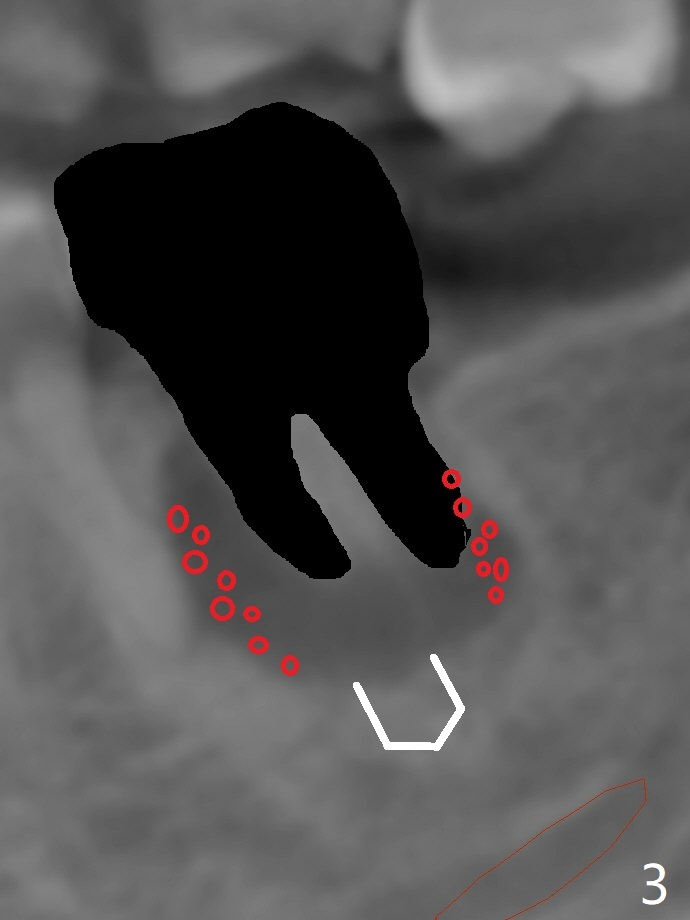

After placement of a 5x11 mm implant and cover screw at #18, allograft mixed with PRF (sticky bone) is placed in the peri-implant space, but it appears that bone density in the apical region (Fig.1 A) is lower than that in the coronal one (C) because of a constriction between the implant and the distal crest (*). Ideally the undercuts (Fig.2 *) of the extraction socket (black area) should be identified. Place bone graft in the undercuts (Fig.3 red circles) after osteotomy (white outlines) and before implant placement! A 4.5x1 mm temporary abutment is placed for an immediate provisional. The 2nd shortcoming of this case is that the implant is placed a little buccal. The papilla mesial to the immediate provisional (Fig.4 P) looks normal 4 days postop (no food impaction is expected when a final restoration is cemented). Additional acrylic (*) was placed to close a buccal gap when the provisional was seated with the temporary abutment. The patient reports loss of a piece of material in 4 days. It must be the additional acrylic, since it is absent 6 weeks postop (Fig.5). The provisional (Fig.5 P) looks wide, probably related to post-extraction gingiva and bone atrophy (Fig.6, 7 *). Bone graft (Fig.6 <) becomes a component of the gingival cuff. The provisional is re-trimmed for better oral hygiene. The gingival cuff is basically healthy 3.5 months postop, although the temporary abutment is loose and the implant is tender to rewinding and winding (Fig.8). The implant seems to remain non-osteointegrated 3.5 months postop (Fig.9). Although the bone density around the implant increases nearly 6 months postop (Fig.10), the implant remains tender when a 5x4(4) mm pair abutment is tightened. The healing abutment is reused. The bone density around the implant increases 11 months postop (Fig.11). Uncover is done with 5.5 mm profile drill. One month post uncover (12 months postop), the implant remains unstable (Fig.12). Prepare sticky bone x1. Make incision for exploration, including retightening the implant after Titanium brush and H2O2 Q-tip rubbing. If needed, a larger and shorter UF implant is a replacement (Fig.13). The implant is removed, cleaned with Titanium brushes and H2O2 in vitro and repositioned 12 months postop (Fig.14: arrow (gaps: post granulation tissue removal)). The gaps are regrafted with sticky bone and covered with PRF membrane and Cytoplast. Although the patient complains of severe pain the first 2-3 postop, the wound is apparently healing 12 days postop. The Cytoplast is exposed asymptomatic 5 weeks postop (Fig.16) and removed (Fig.17). The wound appears to have healed without loss of the bone graft (Fig.18).术后四个月伤口愈合,骨粉几乎没有丢失,有骨小梁形态(图十九:*)。切开,刮匙去骨,有一定硬度,即刻放置修复基台,完全就位(图二十),制备临时牙冠,牙周敷料固定组织瓣(没有缝线)。